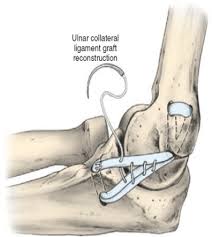

Über 7 millionen englischsprachige bücher. See more ideas about tommy john, tommy, surgery. Sang ho baek gmu pitcher dies after tommy john surgery by matthew stabley • published 1 hour ago education images/universal images group via getty images. Tommy john surgery, named for the major league pitcher who underwent the revolutionary surgery in 1974 and rejuvenated his career, is ulnar collateral ligament reconstruction.the surgery repairs a. The graft is placed through tunnels drilled the ulna (bottom bone) and in the humerus (top bone) of the elbow. The most common graft is the palmaris tendon. Team to lose one of the young prospects on the roster for olympic qualifying next week. George mason university baseball player dies after tommy john surgery sang ho baek, 20, was an incredible teammate who was loved by everyone associated with mason baseball, his coach said.

Sang ho baek gmu pitcher dies after tommy john surgery by matthew stabley • published 1 hour ago education images/universal images group via getty images. The graft is placed through tunnels drilled the ulna (bottom bone) and in the humerus (top bone) of the elbow. Losing justin verlander is massive blow to astros' present and future as big decisions loom with ace justin verlander out for tommy john surgery, the houston astros may have to step back and make difficult decisions about their future. Find the perfect tommy john surgery stock photos and editorial news pictures from getty images. Tommy john surgery is a procedure that reconstructs a torn ulnar collateral ligament. George mason university baseball player dies after tommy john surgery sang ho baek, 20, was an incredible teammate who was loved by everyone associated with mason baseball, his coach said. (cnn)college baseball pitcher sang ho baek died following complications from ulnar collateral ligament reconstruction, commonly known as tommy john surgery, according to a verified gofundme page. Sang ho baek suffered injuries throughout the season and required tommy john surgery, according to a gofundme. Ulnar collateral ligament reconstruction, also known as tommy john surgery (tjs), is a surgical graft procedure where the ulnar collateral ligament in the medial elbow is replaced with either a tendon from elsewhere in the patient's body, or with one from a deceased donor. A pitcher on the george mason university baseball team died saturday at 20 years old, according to the athletic department. Ucl reconstruction or tommy john surgery is performed by using a tendon graft to replace the ucl (see pictures of procedure below). Text us for exclusive photos and videos, royal news, and way more. The most common graft is the palmaris tendon.

Rehabilitation after tommy john surgery. Sang ho baek, 20, had been battling injuries throughout the season, a teammate said, and underwent tommy john surgery, a relatively common procedure for pitchers. Mary mcmahon tommy john surgery is relatively common among baseball pitchers. The graft is placed through tunnels drilled the ulna (bottom bone) and in the humerus (top bone) of the elbow. It uses tendons from elsewhere in the body to repair damage to the.